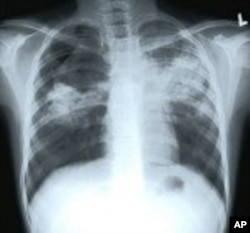

X-ray of patient with tuberculosis

TB is caused by a bacterium known as the Mycobacterium tuberculosis. It’s spread from person to person through tiny airborne droplets of infected sputum. It can affect almost any tissue or organ in the body, with the most common site being the lungs. Basically, it cripples the human immune system, leaving patients vulnerable to deadly bacterial infection.